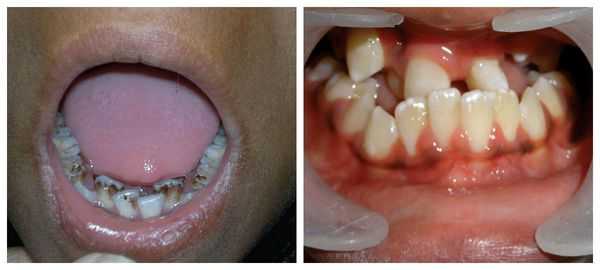

- множество черепно-лицевых аномалий (см. фото выше), включая:

Также характерно уменьшение размера глазных яблок (микрофтальмия), косоглазие, атрезия радужки, катаракта. Около 50% пациентов с болезнью Гольденхара имеют высокое готическое небо, широкий рот (макростомию), расщепление языка, аномальный прикус, отсутствие части зубов. В 40% случаев отмечаются косолапость, аномалии позвоночника (сколиоз, spina bifida), искривление ребер. У 30% больных возникают врожденные патологии внутренних органов: пороки сердца, гипоплазия легких, дисплазия почек.

Перечисленные лицевые аномалии могут сопровождаться нарушением слуха, неправильной закладкой и прорезыванием зубов и другими нарушениями, которые могут повлиять на психофизическое развитие ребёнка.

![Аномалии зубов при синдроме Гольденхара]()